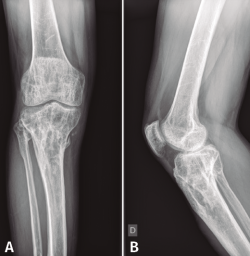

Se trata de un paciente varón de 57 años con antecedente de fractura abierta de tibia-peroné que evolucionó hacia la infección, requiriendo múltiples intervenciones hasta la consolidación de la fractura. Al cabo de 20 años se produce recidiva de la infección presentando fístula productiva al nivel de la cara medial del tercio proximal de la pierna (Figura 1).

Figura 1. Fístula productiva en la cara medial del extremo proximal de la pierna.

En el estudio radiológico (Figura 2) se objetiva fractura consolidada de la tibia con amplia desestructuración ósea.

Figura 2. Radiografías de frente y de perfil de tibia-peroné donde se objetiva fractura consolidada con amplia desestructuración ósea.